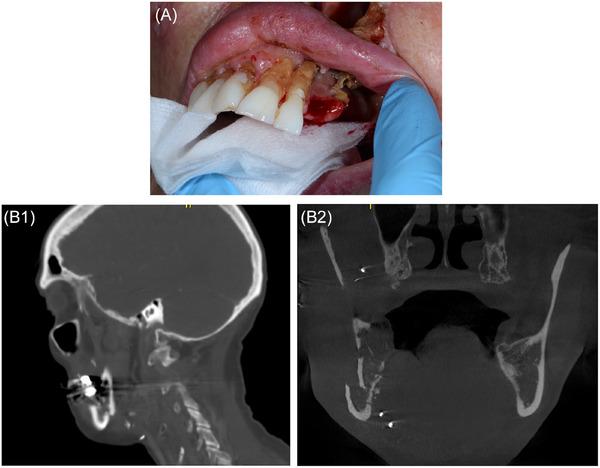

A Targeted Approach to Dental Treatment for Patients Prior To and After Head and Neck Radiation.

This is a narrative review of contemporary radiotherapy for head and neck cancers, the role of pre-radiation dental clearance, and rationale for a targeted approach to pre-radiation treatment. Emphasis is placed on avoiding delay in the start of radiation. The goals of this article are to facilitate communication between the dentist and radiation oncologist, succinctly summarize current recommendations, and give suggestions on what qualifies as high priority dental care in the pre-radiation setting.